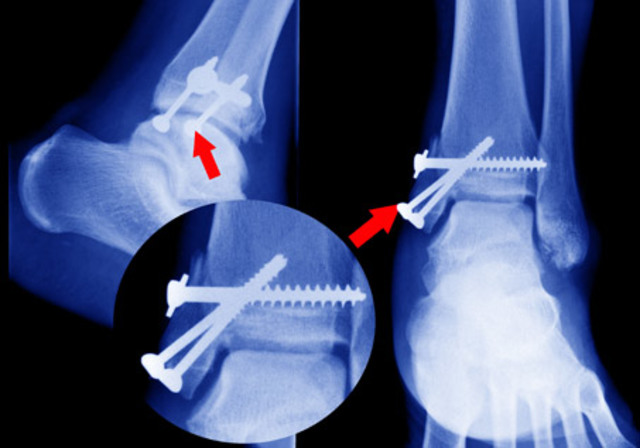

PLACAS OSEAS DE METAL(1900)

El uso de placas metálicas y tornillos para estabilizar los huesos es un procedimiento estándar para los cirujanos ortopédicos de hoy, pero no ha sido siempre el caso. En el pasado, los médicos se limitaban al uso de tirantes y suspensores en el exterior del cuerpo para ayudar a apoyar los huesos fracturados y enfermos.